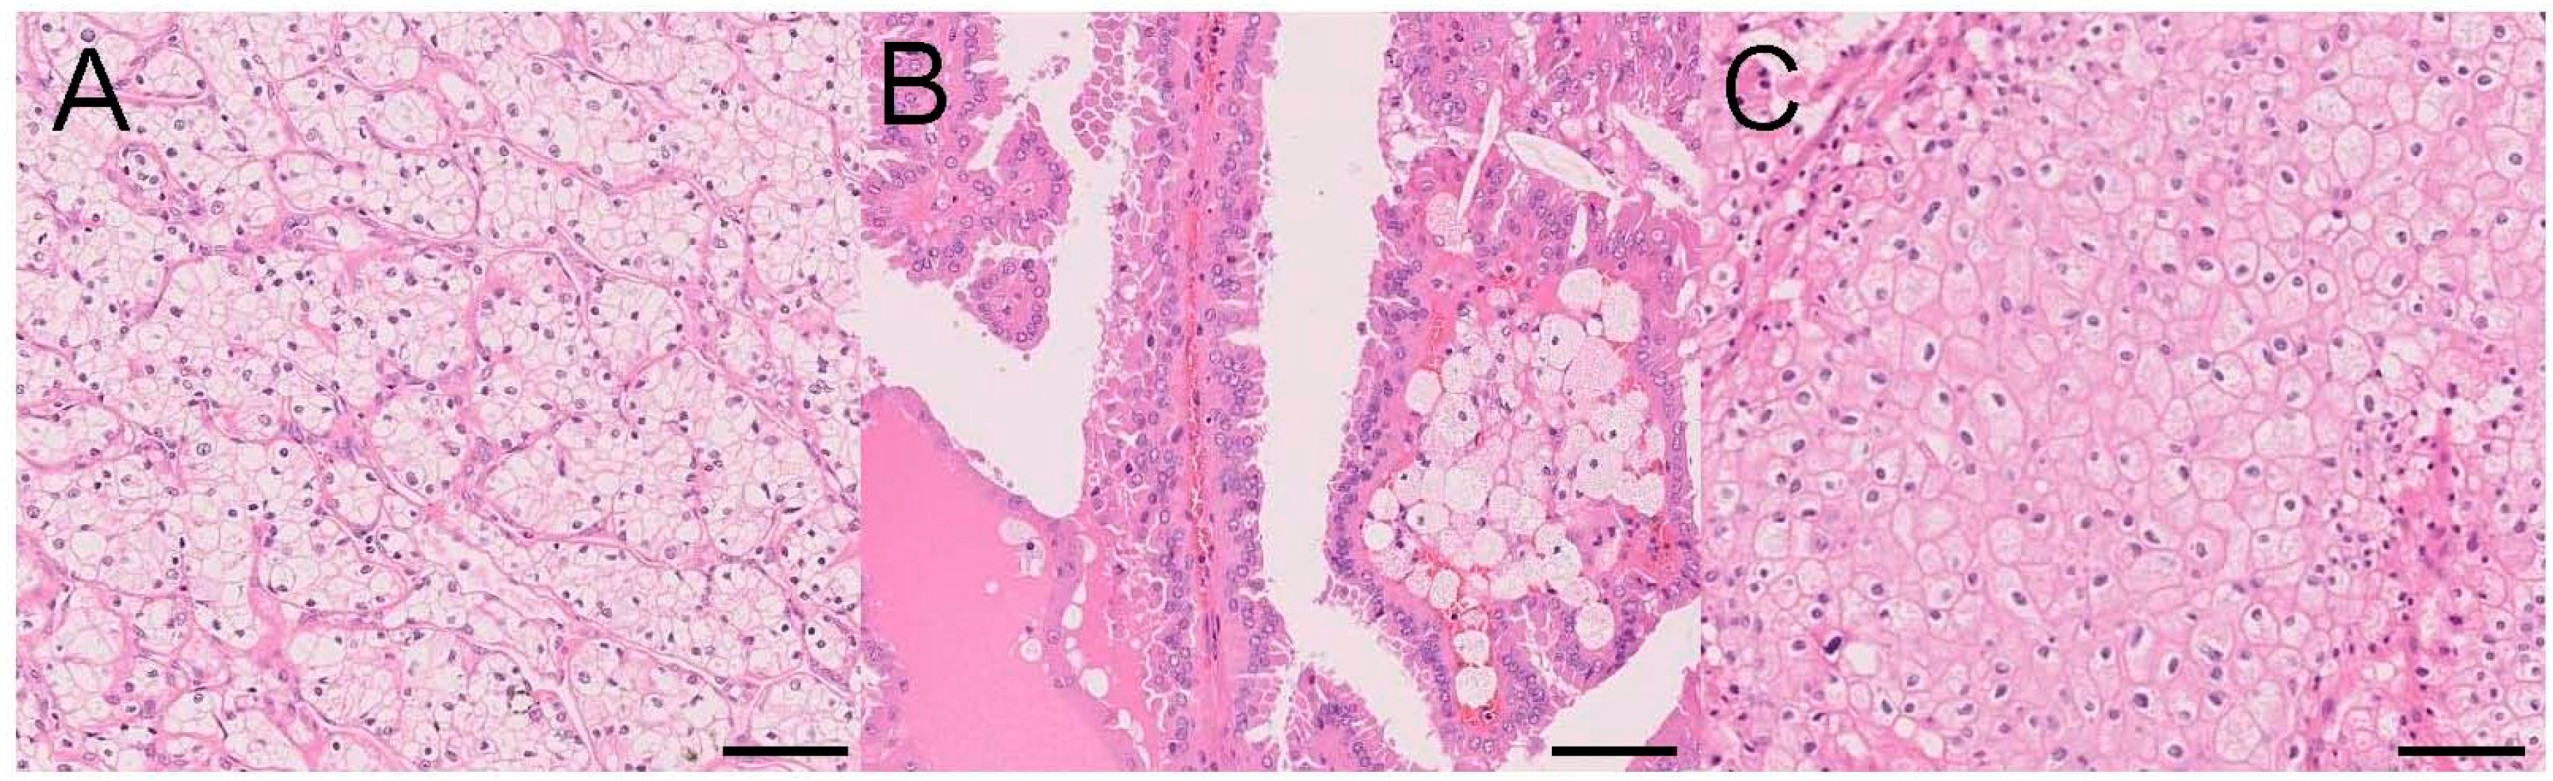

| CCRCC | 65–70% of adult RCCs | Clear/eosinophilic cells with thin-walled, staghorn-shaped vasculature; positive for CAIX and CD10, negative for CK7 and AMACR | Loss of function of VHL, Chr 3p deletion, inappropriate stabilization of HIFs, genetic mutations in PI3K/AKT pathway, mutations of SETD2, BAP1, and MTOR, aggressive CCRCC demonstrating a metabolic shift |

| PRCC | 15–20% of adult RCCs, type 1 shows a better prognosis than type 2 | Papillary structure, foamy macrophages; type 1: scanty cytoplasm; type 2: abundant eosinophilic cytoplasm; positive for CD10, CK7, and AMACR, negative for CAIX  | Gain of Chr 7 and/or Chr 17, loss of Chr Y; type 1: MET alteration; type 2: CDKN2A silencing, SETD2 mutation; three subtypes according to the TCGA, including CIMP-associated aggressive subtype with an FH mutation  |

| ChRCC | 5–7% of adult RCCs, favorable prognosis, Birt-Hogg-Dube syndrome with an FLCN mutation | Prominent cell membrane, irregular nuclei, perinuclear halo, pale to eosinophilic cytoplasm; positive for KIT and CK7, negative for CAIX and CD10 | Loss of Chrs 1, 2, 6, 10, 13, and 17, somatic mutation in mitochondrial DNA, mutations of TP53 and PTEN, imbalanced chromosome duplication (ICD), high TERT expression by DNA rearrangement within the TERT promoter region with kataegis |